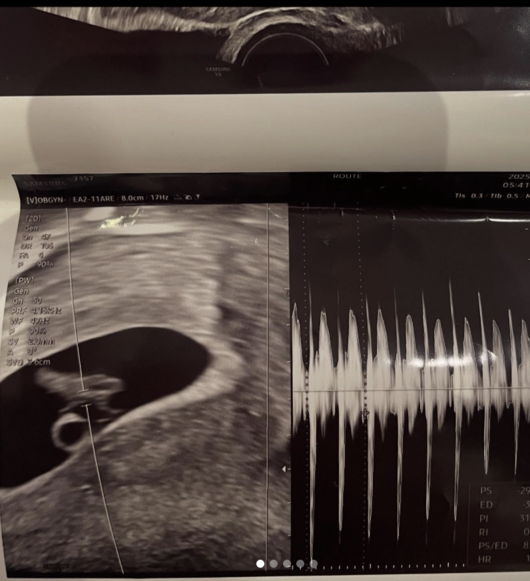

서민재는 A씨의 입장문을 보고 들었던 생각에 대해 “제일 속상했다. 그래도 방어할 수 있다고 생각했는데, 나에게 언질을 안줄수도 있지만, 아이에 대한건 따로 두고 얘기를 하던가 집행유예 기간이니 조심해야하지 않냐고 압박하고, 스트레스 때문에 한번 하혈도 해서 병원을 갔고, 초음파도 매주 받는다”고 현재 건강상태에 대해서도 언급했다.